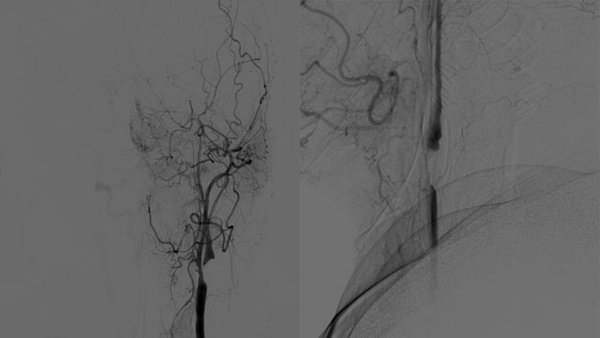

Dive into a curated collection of compelling clinical cases shared by leading experts from LINNC Paris, LINNC Seminars, and LINNC online. Discover a diverse array of complex cases, including aneurysm embolization, AVM/fistula management, stroke interventions, and cSDH treatment. Each case study provides an in-depth exploration of advanced procedures, innovative techniques, and their real-world applications in diagnosing and managing neurovascular conditions.

«Catch» the displacement of the WEB!

AneurysmsIntrasacular devices